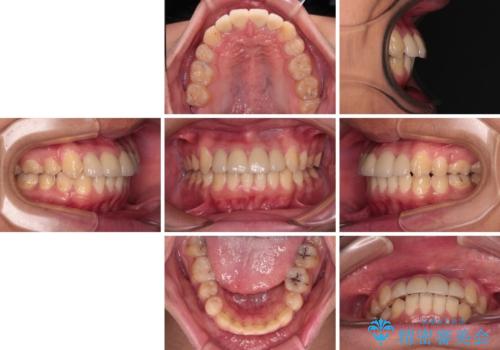

矯正治療は、むし歯が酷く抜歯が望ましい歯を1本抜歯して、ワイヤー装置にて整えることとしました。

矯正治療後は上顎前歯4本をオールセラミッククラウンにて補綴治療を行うこととしました。

むし歯が多かったため、ワイヤー矯正中に処置したむし歯が悪化することが懸念されましたが、歯磨きをしっかりと行ってくれたため、とても良好な状態を維持することができました。